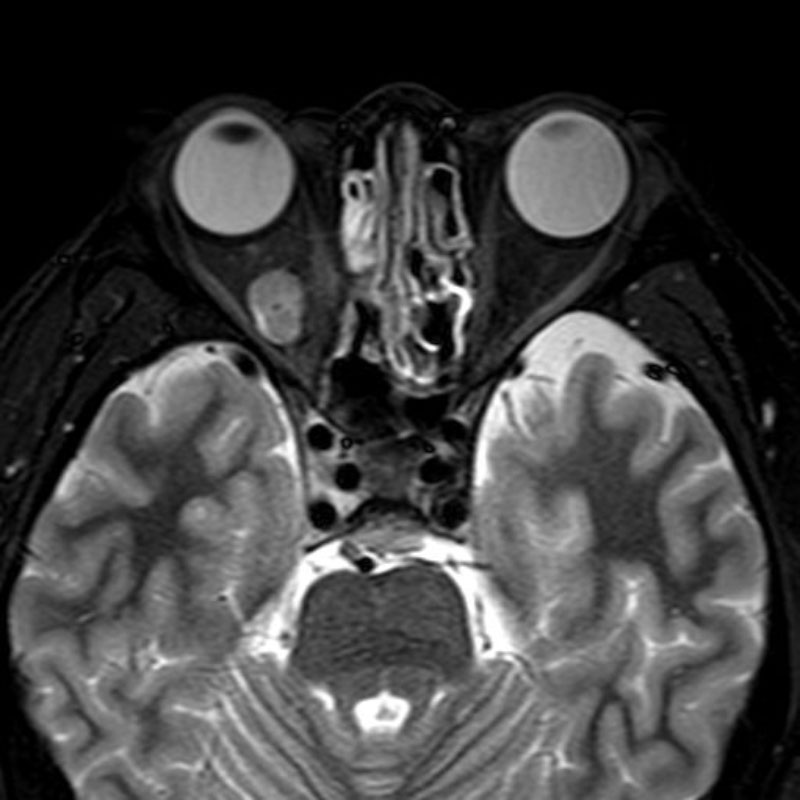

No.’25_41 手術前1

No.’25_41 手術前2